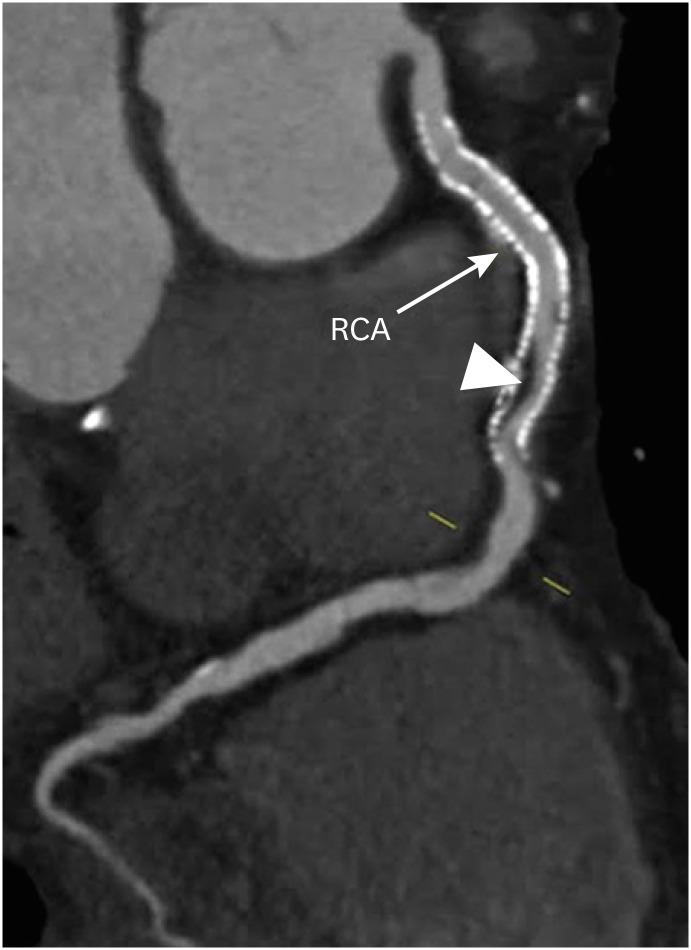

冠状动脉疾病报告与数据系统:全面综述。

Coronary Artery Disease Reporting and Data System: A Comprehensive Review.

The Coronary Artery Disease Reporting and Data System (CAD-RADS) is a standardized reporting method for coronary computed tomography angiography (CCTA). It summarizes the findings of CCTA in 6 categories ranging from CAD-RADS 0 (complete absence of coronary artery disease) to CAD-RADS 5 (total occlusion of at least one vessel). It is applied on per patient basis for the highest grade of the stenotic lesion. The CAD-RADS also provides category-specific treatment recommendations, helping patient management. The main objectives of the CAD-RADS are to improve the consistency in reporting, facilitate the communication between interpreting and referring clinicians, recommend the best course of patient management, and produce consistent data for quality improvement, research and education. However, CAD-RADS has many limitations, resulting into the misclassification of the observed findings, misinterpretation of the final category, and misguidance for the treatment based upon the single score. In this review, the authors discuss the CAD-RADS categories and modifiers, along with the strengths and limitations of this new classification system.

冠状动脉疾病报告与数据系统(CAD-RADS)是一种用于冠状动脉计算机断层扫描血管造影(CCTA)的标准化报告方法。它将CCTA的结果总结为6类,范围从CAD-RADS 0(完全不存在冠状动脉疾病)到CAD-RADS 5(至少一根血管完全闭塞)。它针对每位患者应用于狭窄病变的最高等级。CAD-RADS还提供特定类别的治疗建议,有助于患者管理。CAD-RADS的主要目标是提高报告的一致性,促进解读医生与转诊医生之间的沟通,推荐最佳的患者管理方案,并产生用于质量改进、研究和教育的一致数据。然而,CAD-RADS有许多局限性,导致观察结果的错误分类、最终类别的错误解读以及基于单一分数的治疗误导。在本综述中,作者讨论了CAD-RADS类别和修饰符,以及这个新分类系统的优点和局限性。